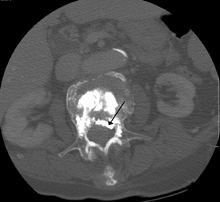

During the procedure, bone cement is injected with a biopsy needle into the collapsed or fractured vertebra. The needle is placed with fluoroscopic x-ray guidance. The cement (most commonly PMMA, although more modern cements are used as well) quickly hardens and forms a support structure within the vertebra that provide stabilization and strength. The needle makes a small puncture in the patient's skin that is easily covered with a small bandage after the procedure.[19]